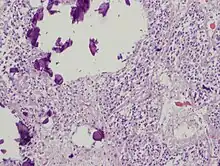

The pineal body in humans consists of a lobular parenchyma of pinealocytes surrounded by connective tissue spaces. The gland's surface is covered by a pial capsule.

The pineal gland consists mainly of pinealocytes, but four other cell types have been identified. As it is quite cellular (in relation to the cortex and white matter), it may be mistaken for a neoplasm.[18]

Pinealocytes | The pinealocytes consist of a cell body with 4–6 processes emerging. They produce and secrete melatonin. The pinealocytes can be stained by special silver impregnation methods. Their cytoplasm is lightly basophilic. With special stains, pinealocytes exhibit lengthy, branched cytoplasmic processes that extend to the connective septa and its blood vessels. |

Interstitial cells | Interstitial cells are located between the pinealocytes. They have elongated nuclei and a cytoplasm that is stained darker than that of the pinealocytes. |

Perivascular phagocyte | Many capillaries are present in the gland, and perivascular phagocytes are located close to these blood vessels. The perivascular phagocytes are antigen presenting cells. |

Pineal neurons | In higher vertebrates neurons are usually located in the pineal gland. However, this is not the case in rodents. |

Peptidergic neuron-like cells | In some species, neuronal-like peptidergic cells are present. These cells might have a paracrine regulatory function. |